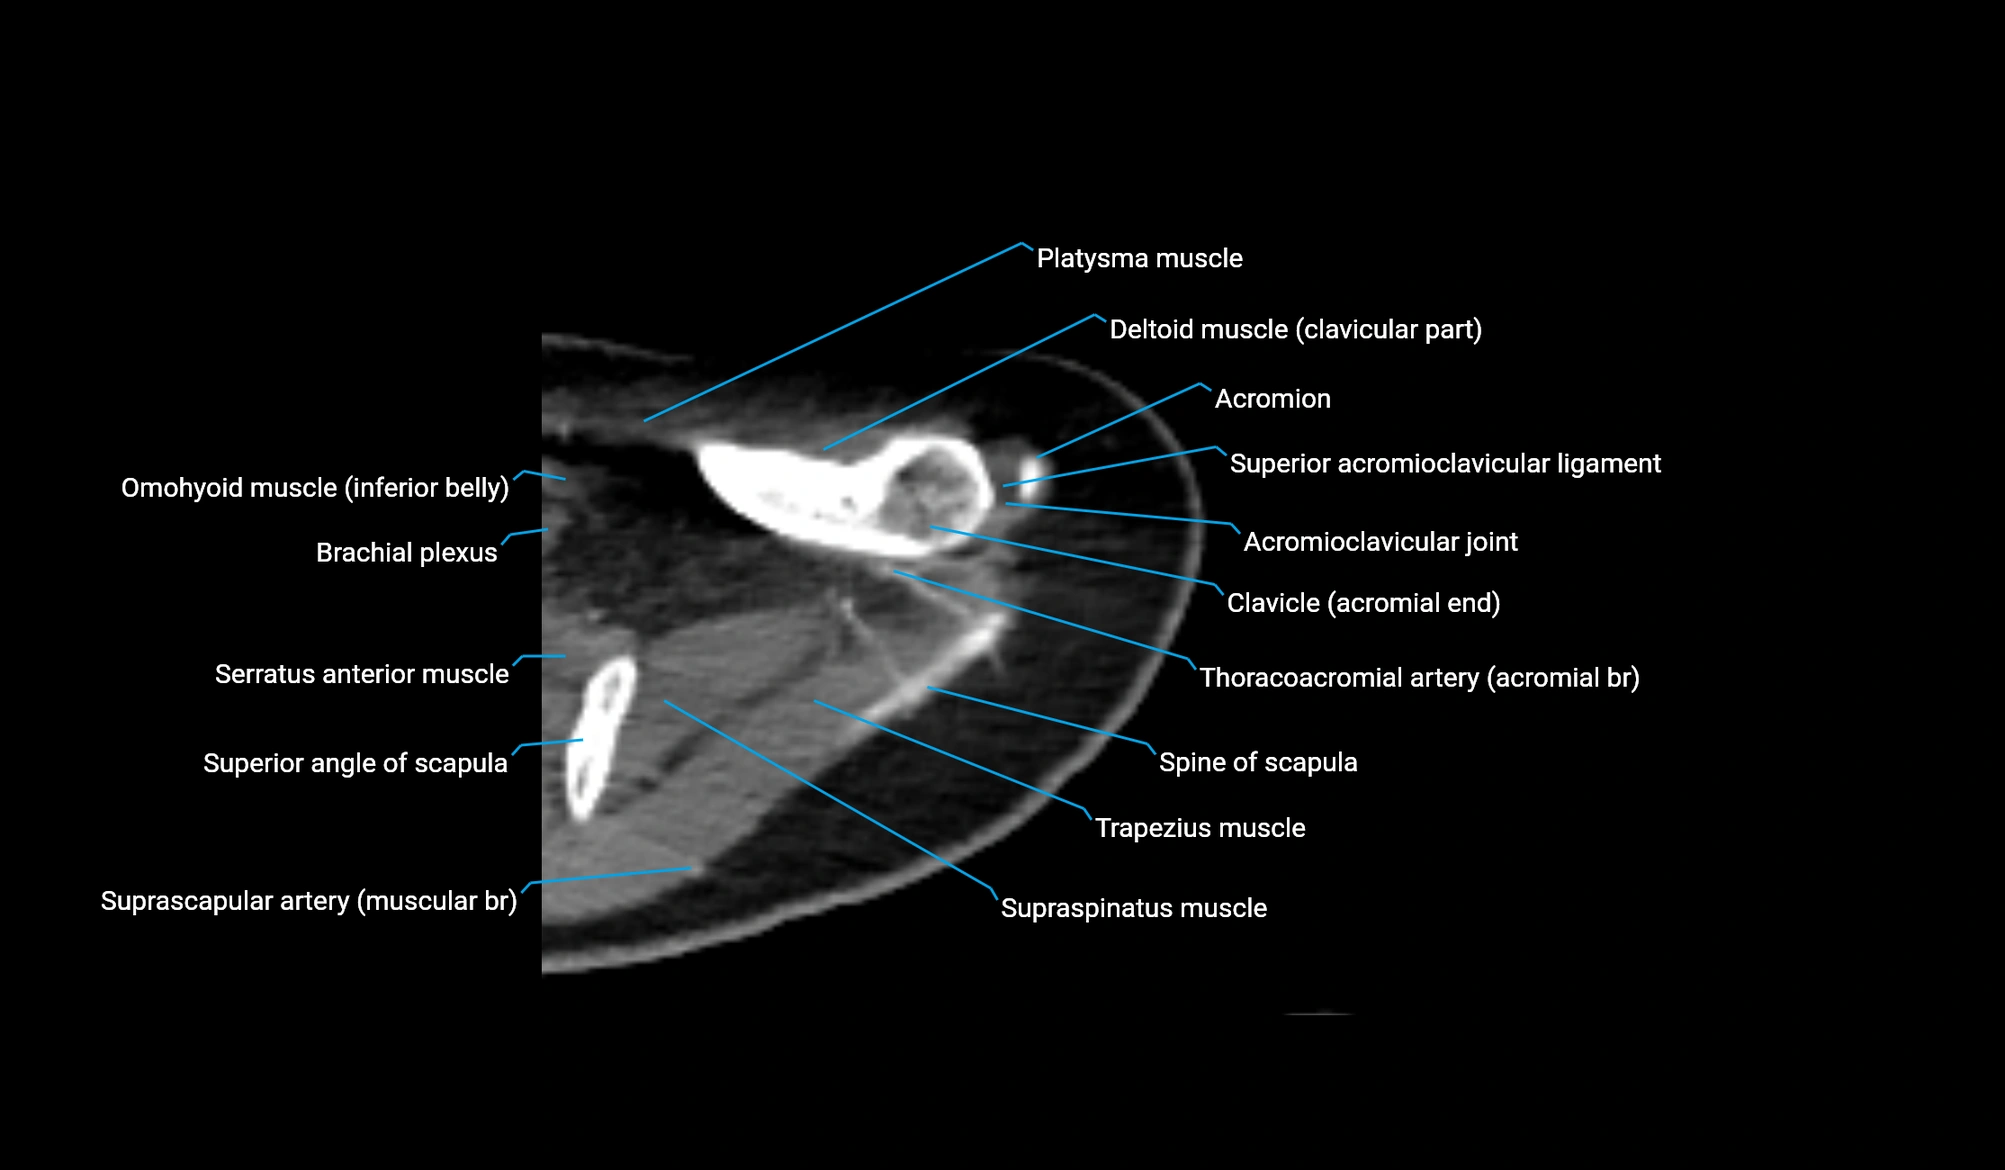

- Acromioclavicular joint

- Acromioclavicular ligament

- Acromion process of scapula

- Brachial plexus

- Clavicular part of deltoid muscle

- Inferior belly of omohyoid muscle

- Spine of scapula

- Superior acromioclavicular ligament

- Superior angle of scapula

- Supraspinatus muscle